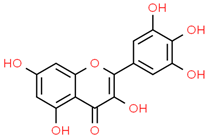

| 10 | Myricetin | 5281672 | C15H10O8 | 318.23 | C1=C(C=C(C(=C1O)O)O)C2=C(C(=O)C3=C(C=C(C=C3O2)O)O)O |  |